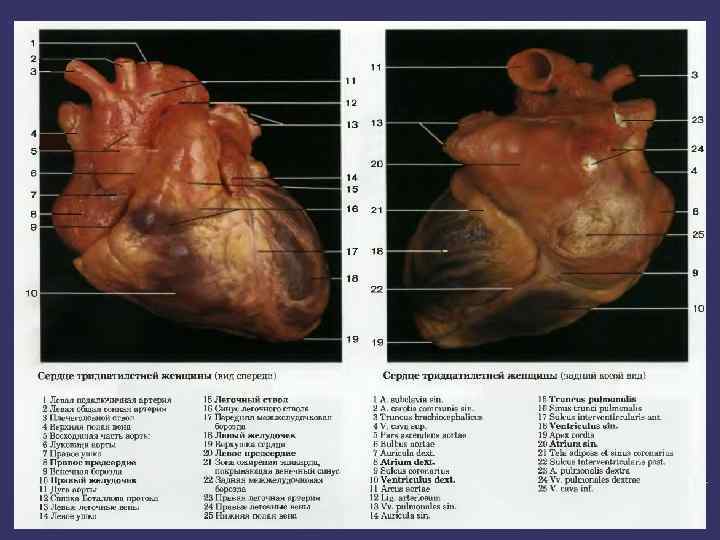

Жүрек Алдыңғы көрінісі Артқы көрінісі

➲ ➲ ➲ Зерттеу барысында жүрек камераларының кеуде қабырғасына жатқызылуын елестетіп алуымыз керек. Оң жақ қарынша жүректің алдыңғы беткейінде орналасады. Бұл камера өкпе артериясымен кеуденің сол және артқы жағында сына тәрізді жазықтықты құрастырады. Оң жақ қарыншаның төменгі бөлігі кеуде денесінің төстің семсер тәрізді өсіндісімен байланысқан жерінен төмендеу орналасқан. Оң жақ қарынша жоғарыға қарай тарылады және III- қабырға мен төстің арасындағы шеміршек деңгейінде өкпе артериясына өтеді. Сол жақ қарынша оң жақ қарыншадан солға және артқа қарай орналасқан. Жүректің алдыңғы беткейінің кіші бөлігін ғана алып жатады. Клиникалық жағынан бұл өте маңызды, өйткені ол жұректің сол жақ бөлігін құрайды және жоғарғы серпілістің негізгі көзі болып табылады. Жоғарғы серпіліс бұл жүректің систола кезінде кеуде қабырғасына соғуын сипатайды және V қабырға арасында болады.

Қорытынды Қорыта айтар болсақ зерттеу барысында жүрек камераларының кеуде қабырғасына жатқызылуын елестетіп алуымыз керек. Оң жақ қарынша жүректің алдыңғы беткейінде орналасады. Бұл камера өкпе артериясымен кеуденің сол және артқы жағында сына тәрізді жазықтықты құрастырады. Сол жақ қарынша оң жақ қарыншадан солға және артқа қарай орналасқан. Жүректің алдыңғы беткейінің кіші бөлігін ғана алып жатады. Клиникалық жағынан бұл өте маңызды, өйткені ол жұректің сол жақ бөлігін құрайды және жоғарғы серпілістің негізгі көзі болып табылады. Жоғарғы серпіліс бұл жүректің систола кезінде кеуде қабырғасына соғуын сипатайды және V қабырға арасында болады.